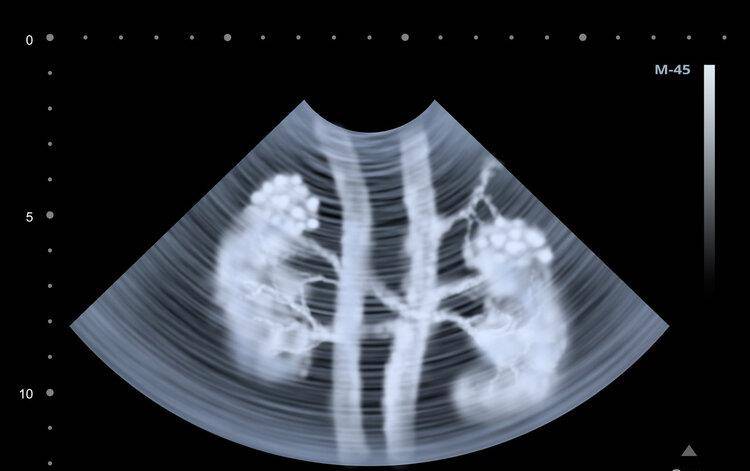

文章图片